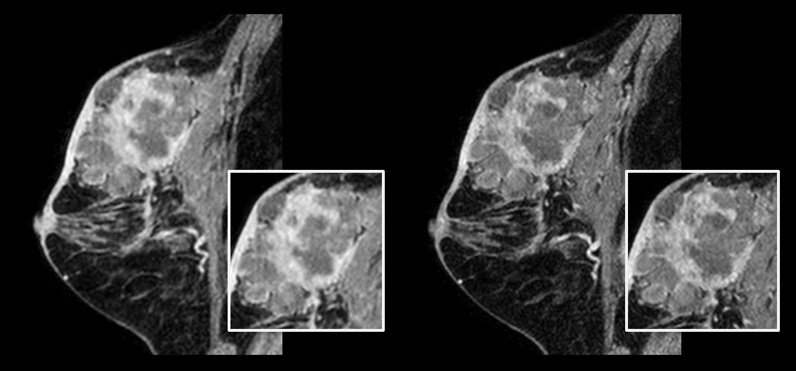

Paziente con cancro della mammella.

A sinistra: scansione in 3D mDIXON XD convenzionale con dimensione voxel isotropica di 1,0 mm e tempo di scansione di 2,22 minuti

A destra: scansione in 3D mDIXON XD mediante Compressed SENSE con dimensione voxel isotropica di 0,8 mm e tempo di scansione di 2,21 minuti.

Per gentile concessione del centro ospedaliero di Kurashiki, Okayama (Giappone)

Nella scansione della mammella, l'alta risoluzione è importante perché consente di identificare lesioni mammarie molto piccole. Perciò, abbiamo bisogno di un'elevata risoluzione spaziale nelle immagini in 2D con pesatura T1 e T2, oltre che di un tempo di scansione ridotto. Compressed SENSE ci ha permesso di aumentare la risoluzione spaziale a vantaggio dell'affidabilità diagnostica."

Dott. Takashi Koyama, radiologo diagnostico e direttore del reparto di radiologia del Kurashiki Central Hospital (Giappone)